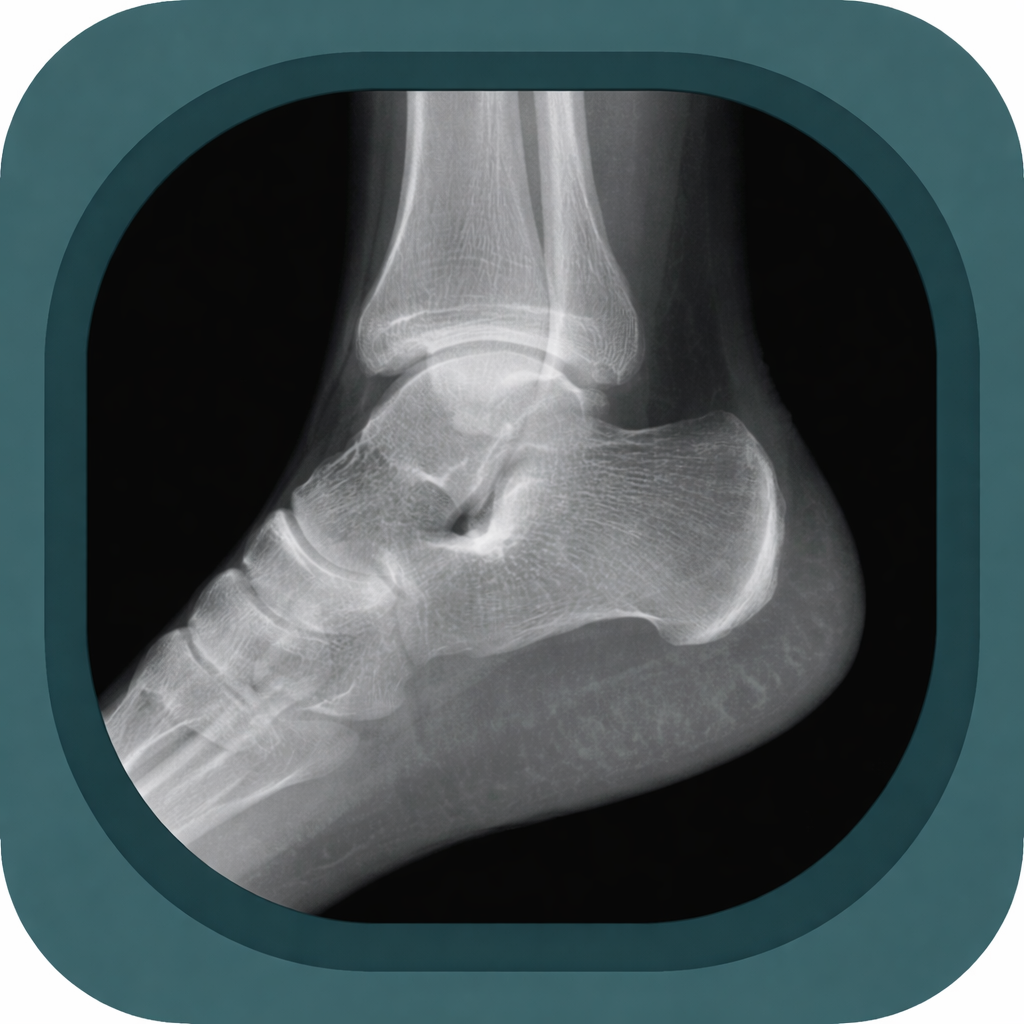

Explore high-quality X-ray anatomy from head to toe. Our database features carefully labelled images to visualize fine structures—perfect for radiologists, students, and surgeons.